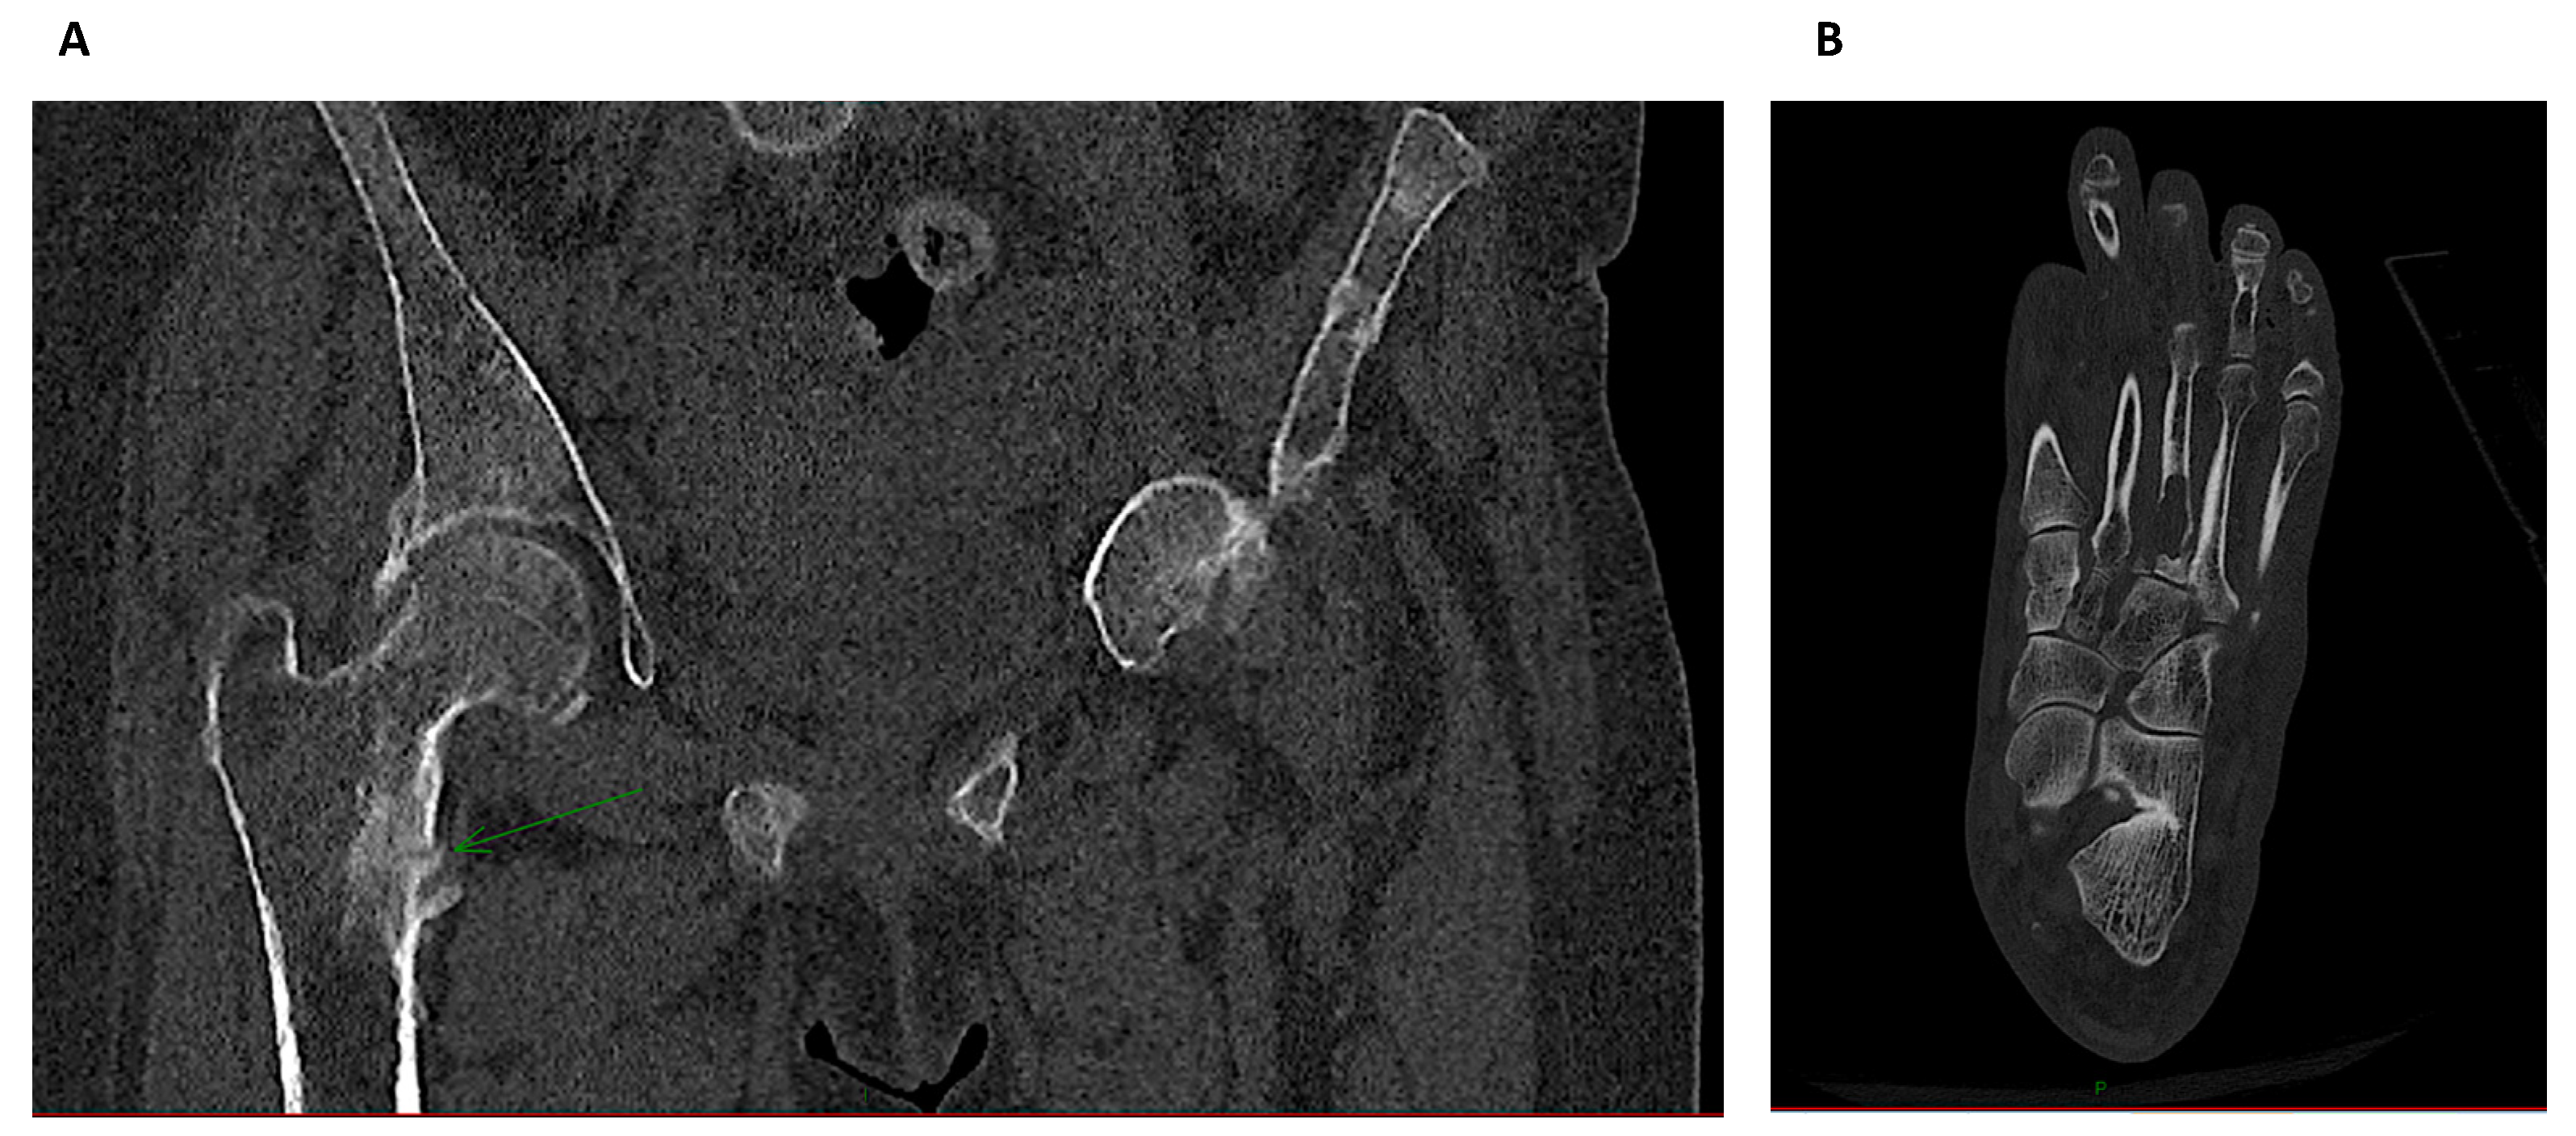

3.5. Quantitative Computerized Tomography

3.6. High Resolution-Peripheral Quantitative Computerized Tomography (HR-pQCT)

- Cejka, D.; Patsch, J.M.; Weber, M.; Diarra, D.; Riegersperger, M.; Kikic, Z.; Krestan, C.; Schueller-Weidekamm, C.; Kainberger, F.; Haas, M. Bone microarchitecture in hemodialysis patients assessed by HR-pQCT. Clin. J. Am. Soc. Nephrol. 2011, 6, 2264–2271. [Google Scholar] [CrossRef] [PubMed]

- Negri, A.L.; Del Valle, E.E.; Zanchetta, M.B.; Nobaru, M.; Silveira, F.; Puddu, M.; Barone, R.; Bogado, C.E.; Zanchetta, J.R. Evaluation of bone microarchitecture by high-resolution peripheral quantitative computed tomography (HR-pQCT) in hemodialysis patients. Osteoporos. Int. 2012, 23, 2543–2550. [Google Scholar] [CrossRef]

- Sharma, A.K.; Toussaint, N.D.; Masterson, R.; Holt, S.G.; Rajapakse, C.S.; Ebeling, P.R.; Mohanty, S.T.; Baldock, P.; Elder, G.J. Deterioration of Cortical Bone Microarchitecture: Critical Component of Renal Osteodystrophy Evaluation. Am. J. Nephrol. 2018, 47, 376–384. [Google Scholar] [CrossRef]

| HR-pQCT | Trabecular architecture Volumetric BMD | Hip, distal radius, distal tibia | Secondary Hyperparathyroidism | All and research |